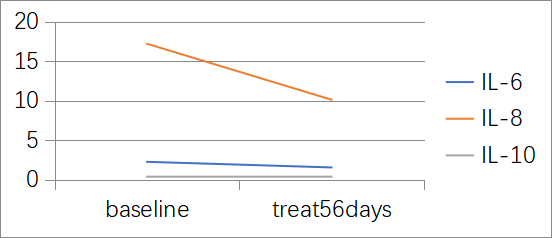

淫羊藿素软胶囊治疗后的各项指标变化

1. AFP值变化

用药后3个月AFP明显下降,用药10个月后AFP降至10 ng/mL以下,详见图1。

图1. AFP水平变化

2. TNF-α与IFN-γ变化

用药后TNF-α下降明显,IFN-γ呈上升趋势,详见图2。

图2. TNF-α和IFN-γ水平变化

3. IL-6、IL-8和IL-10变化

用药后IL-6和IL-8下降明显,详见图3。

图3. IL-6、IL-8和IL-10水平变化